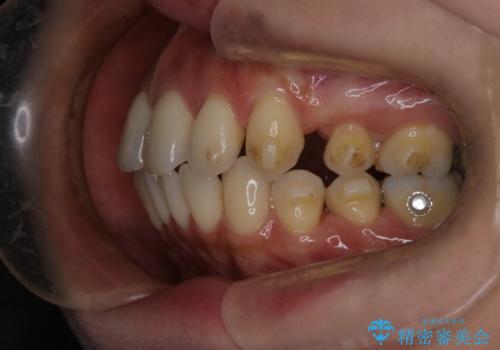

- 上の前歯の突出感を気にして来院された患者様です。

目立たない装置を希望とのことで、上顎左右第一小臼歯を抜歯し、インビザラインにて矯正治療を行うこととしました。